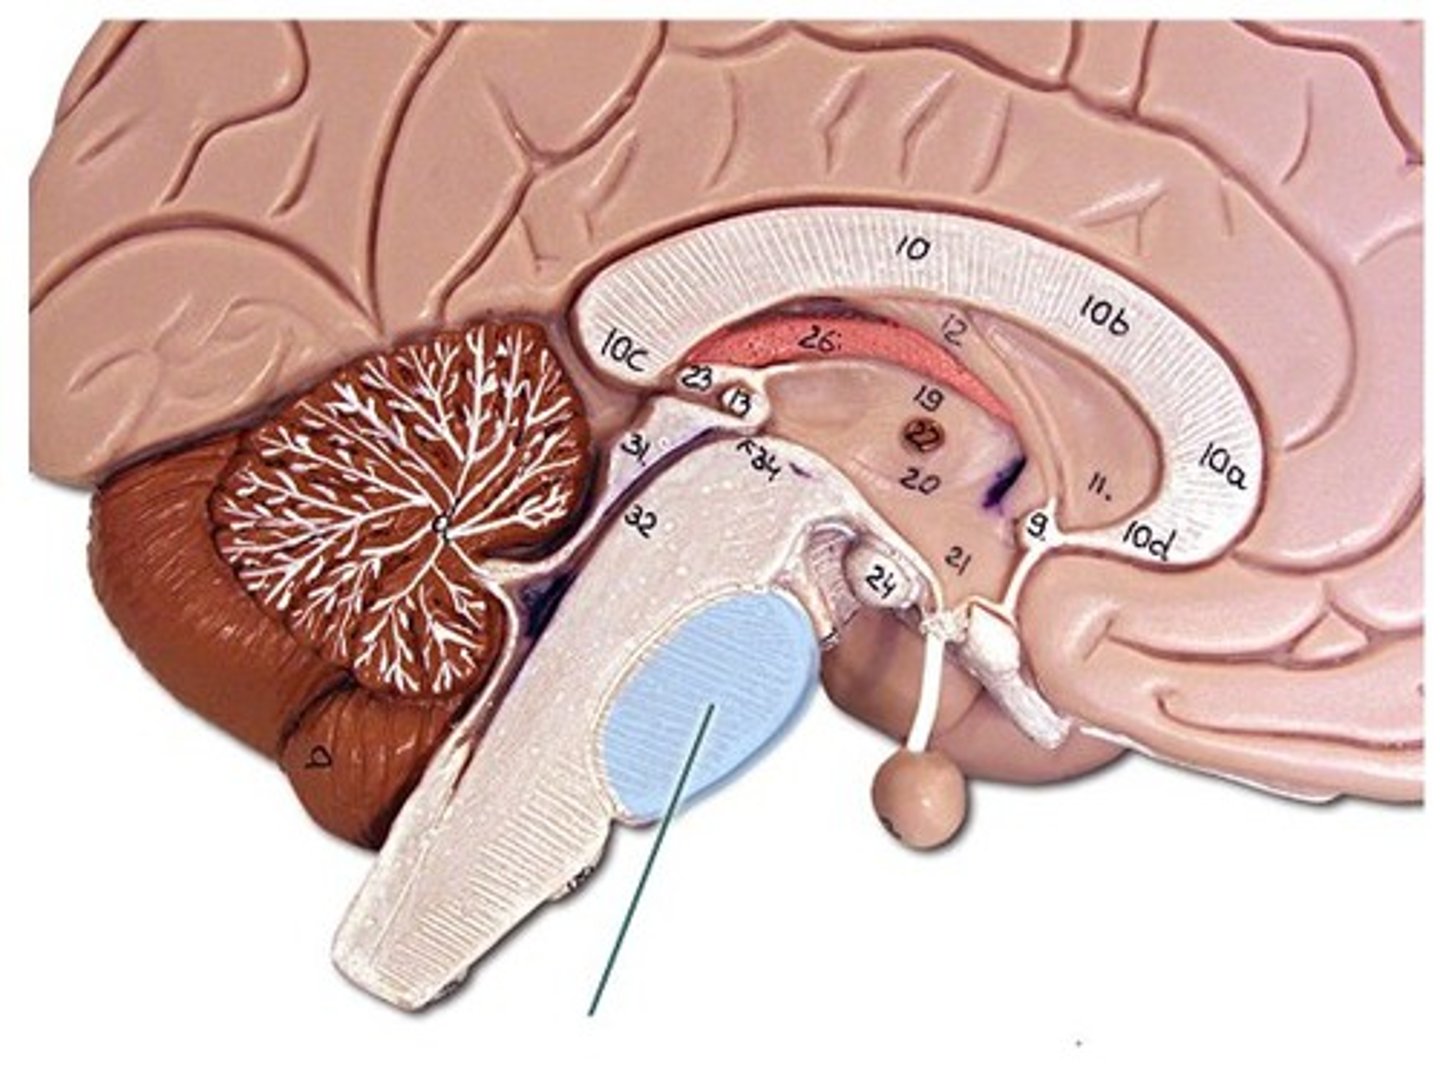

34 Terms

1

New cards

longitudinal fissure

2

New cards

frontal lobe

3

New cards

temporal lobe

4

New cards

parietal lobe

5

New cards

occipital lobe

6

New cards

central sulci

7

New cards

lateral sulci

8

New cards

gyri

9

New cards

cerebrum

10

New cards

corpus callosum

11

New cards

lateral ventricles

12

New cards

3rd ventricle

13

New cards

4th ventricle

14

New cards

cerebellum

15

New cards

thalamus

16

New cards

hypothalamus

17

New cards

midbrain

18

New cards

pons

19

New cards

medulla oblongata

20

New cards

cerebral aqueduct

21

New cards

I.

Olfactory

22

New cards

II.

Optic

23

New cards

III

Oculomotor

24

New cards

IV.

Trochlear

25

New cards

V.

Trigeminal

26

New cards

VI.

Abducens

27

New cards

VII.

Facial

28

New cards

VIII.

Vestibulocochlear

29

New cards

IX

Glossopharngeal

30

New cards

X.

Vagus

31

New cards

XI

Accessory

32

New cards

XII

Hypoglossal